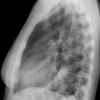

Case 3 RM & UL pneum PA

Date: 07/04/2004

Views: 5881